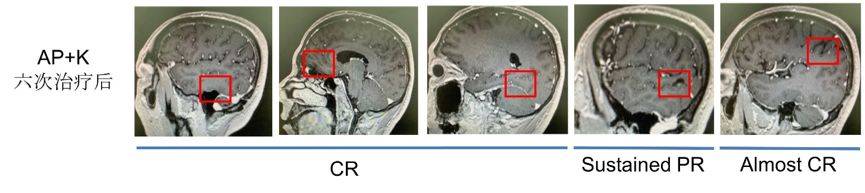

头颅双倍剂量增强MRI(2019.1.22)

双侧颞叶、左侧海马区、左侧顶叶、右侧额叶可见多发结节样强化灶,考虑转移瘤。

图3. 头颅双倍剂量增强MRI(2019.01.22)

两次化疗+ pembrolizumab后,我们发现患者左侧颞叶、顶叶环形强化结节较前减小,周围水肿带范围较前减小。左侧海马区、右侧颞叶及额叶,强化结节较前明显减小,部分呈点状、部分显示不清。胸部CT提示肺部原发灶变化不明显。

继续这个治疗方案,于2019年4月10日至2019年5月14日对患者再行2次K药联合化疗治疗。再次行头颅增强核磁结果提示:左侧颞叶、顶叶强化结节较前减小,周围水肿带范围较前减小。原左侧海马区、右侧颞叶及额叶、右侧小脑半球强化结节未见明确显示。胸部CT结果提示右上肺结节较前减小(约25.7%),但未达到PR。

图4. 头颅双倍剂量增强MRI(基线以及两次和四次联合治疗后)

图7. 头颅双倍剂量增强MRI(六次联合治疗后)

患者治疗至今,头颅转移灶大多已达到CR,肺部肿瘤无明显复发征象,肿瘤标志物在4次术前治疗后一直处于正常范围。后期给予患者培美曲塞单药+pembrolizumab维持治疗。